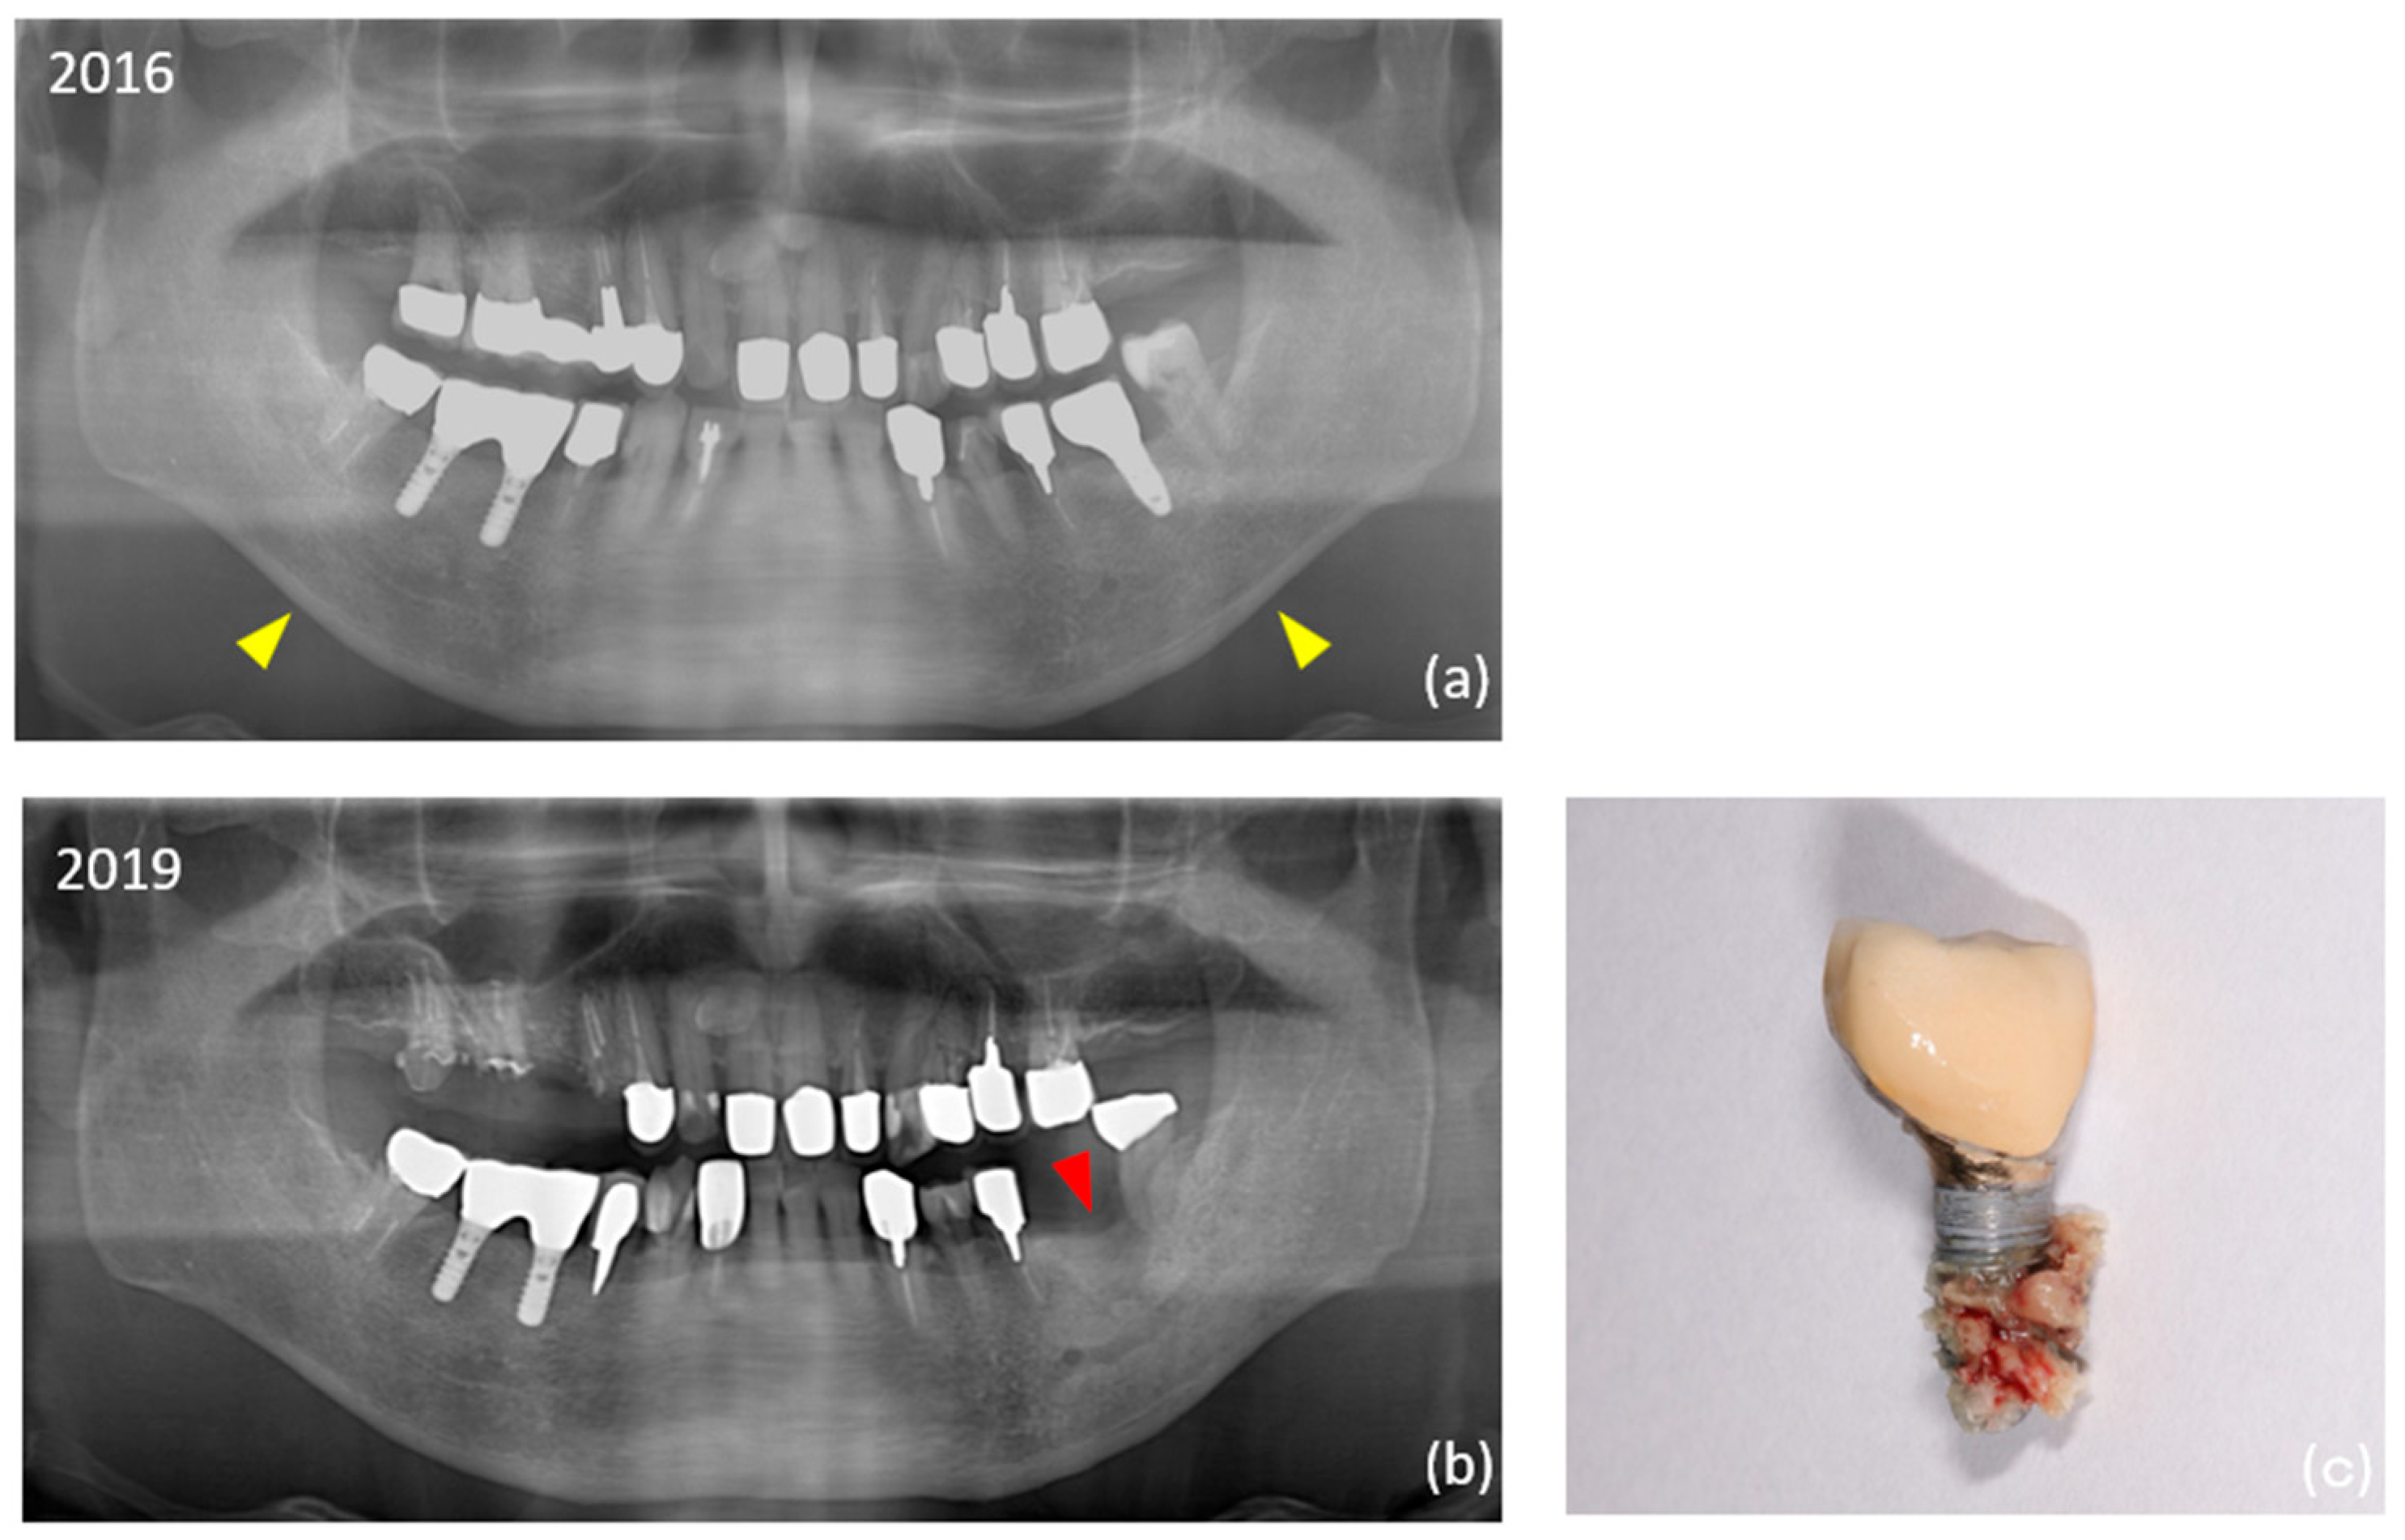

- Seki, K.; Namaki, S.; Kamimoto, A.; Hagiwara, Y. Medication-related osteonecrosis of the jaw subsequent to periimplantitis: A case report and literature review. J. Oral Implantol. 2021, 47, 502–510. [Google Scholar] [CrossRef] [PubMed]

- Seki, K.; Hagiwara, Y. Peri-implant medication-related osteonecrosis of the jaw developed during long-term maintenance: A case report. J. Dent. Sci. 2022, 17, 576–577. [Google Scholar] [CrossRef]

| 13 | 79 | Female | 4 | B | Alendronate | Oral | 1 week | 4 | Astra (4) | PI-MRONJ (#14, #16, #36) |

| 20 | 87 | Male | 3 | A | Minodronate | Oral | Daily | 2 | Nobel Biocare (1) | PI-MRONJ (#36) |